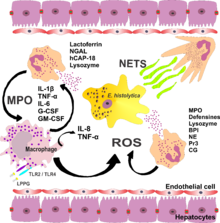

As to the pathogenesis of Amoebic liver abscess we find that trophozoites adhere to colonic epithelial cells using Gal/GalNAc lectin.They release cysteine proteinases that degrade extracellular matrix proteins, allowing invasion into submucosal tissues.From the colon, trophozoites enter mesenteric venules, then the portal circulation, reaching the liver.Inside liver, trophozoites induce apoptosis of hepatocytes, leading to necrosis.Most commonly affects the right lobe of the liver due to its vascular supply[6][7][8][2]